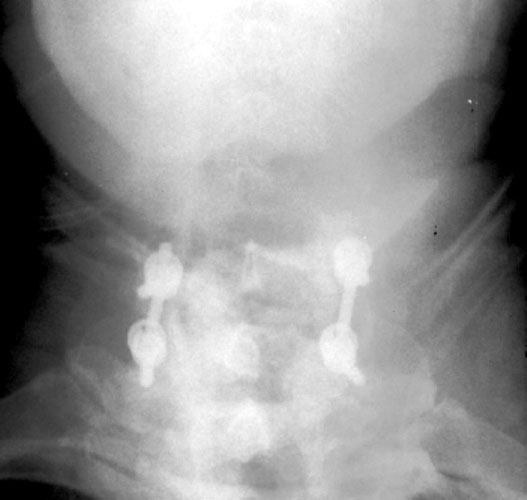

Slipped Rod

65 y.o male with prior surgery 23 years ago, secondary to trauma involving

C4-5, C5-6 ACDF procedures. Now is 1 yr s/p bilateral C5 and C6 foraminotomy and

C6-C7 posterior fusion and right iliac crest bone graft for persistent numbness

and tingling f or 2 years.

Radiographs obtained 5 months post-operatively demonstrate normal

C6-7 fusion without evidence of hardware failure. |